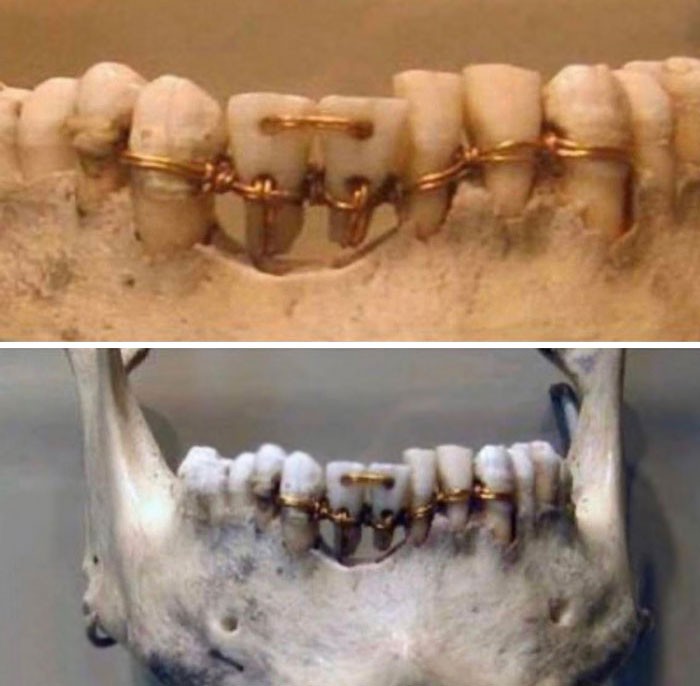

Jakarta - Deretan foto ini dibagikan netizen di media sosial, mulai dari Twitter hingga forum Reddit. Awas, siap-siap bergidik melihatnya.

Awas Foto Ini Bisa Bikin Bergidik